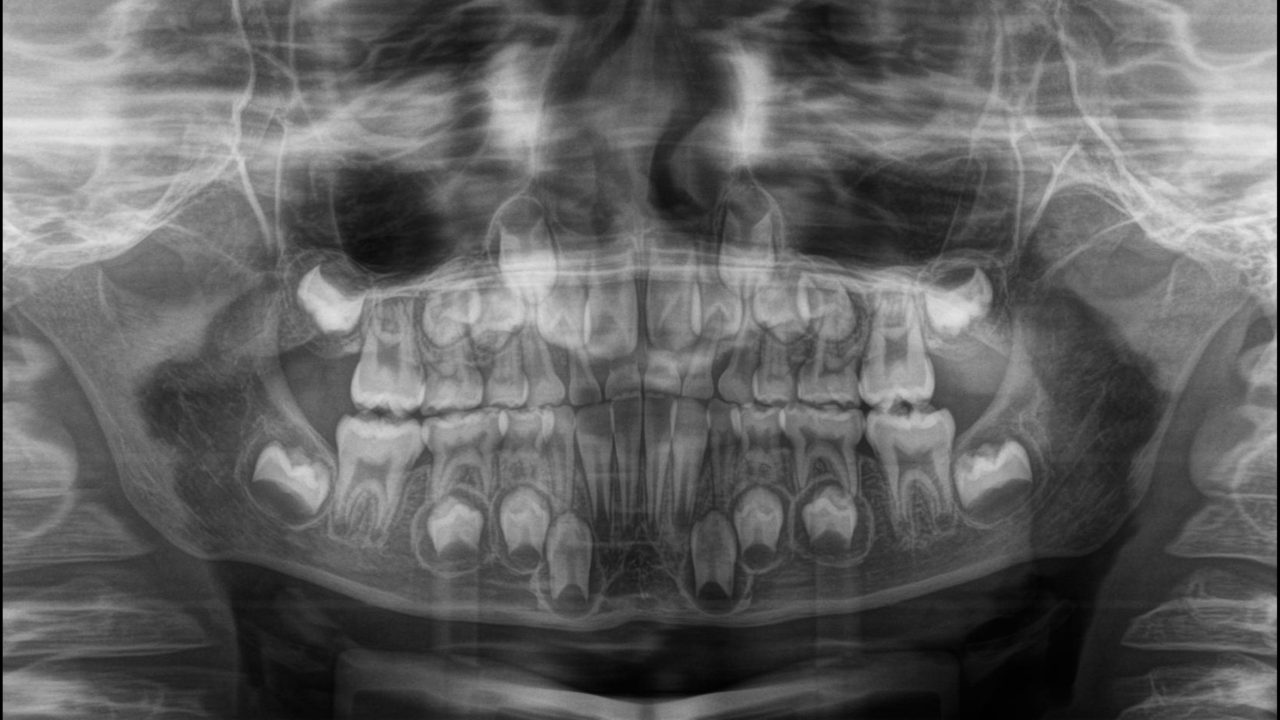

初診 2017.12.21

6歳3か月、反対咬合(受け口)を主訴に来院。 ムーシールドによる機能的矯正開始。

初診 レントゲン

歯の本数、位置に以上は認めない。